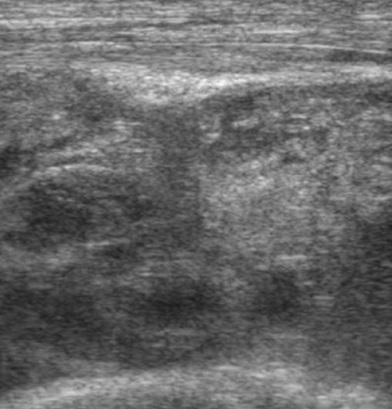

Znacznego stopnia przerost błony maziowej w zachyłku nadrzepkowym z widocznymi wzmożonymi echami przepływów w badaniu Power Doppler – aktywny proces zapalny w przebiegu RZS.

W konsekwencji prowadzi to do trwałych zwyrodnień i zniekształceń stawów. Badanie USG wykorzystywane jest coraz częściej w diagnostyce RZS, gdyż dostarcza informacji na długo wcześniej od objawów prezentowanych na klasycznym zdjęciu rentgenowskim i badaniu tomograficznym. Dzięki głowicom o wysokiej częstotliwości, badanie USG pozwala na jakościową ocenę przerostu błony maziowej wraz z oszacowaniem jej aktywności zapalnej w badaniach dopplerowskich oraz dokładne obejrzenie powierzchni stawowych pod kątem wykrycia nadżerek. W przypadku pacjentów ze stwierdzonym i leczonym RZS należy podkreślić nieocenioną rolę badania USG z funkcją dopplerowską. Pozwala ona bowiem potwierdzić lub ocenić stopień aktywności choroby, ale także wcześnie wykazać zaostrzenie choroby, jeszcze zanim dojdzie do pojawienia się typowych, klinicznych objawów zaostrzenia.